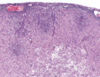

Name & describe the pathologic process in this image.

Neuronophagia

Migroglia surround necrotic neuron & phagocytose it to remove the debris